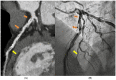

Recently, medical radiology has undergone significant improvements in patient management due to advancements in image acquisition by the last generation of machines, data processing, and the integration of artificial intelligence. In this way, cardiovascular imaging is one of the fastest-growing radiological subspecialties. In this study, a compressive review was focused on addressing how and why CT and MR have gained a I class indication in most cardiovascular diseases, and the potential impact of tissue and functional characterization by CT photon counting, quantitative MR mapping, and 4-D flow. Regarding rectal imaging, advances in cancer imaging using diffusion-weighted MRI sequences for identifying residual disease after neoadjuvant chemoradiotherapy and [18F] FDG PET/MRI were provided for high-resolution anatomical and functional data in oncological patients. The results present a large overview of the approach to the imaging of diffuse and focal liver diseases by US elastography, contrast-enhanced US, quantitative MRI, and CT for patient risk stratification. Italy is currently riding the wave of these improvements. The development of large networks will be crucial to create high-quality databases for patient-centered precision medicine using artificial intelligence. Dedicated radiologists with specific training and a close relationship with the referring clinicians will be essential human factors.